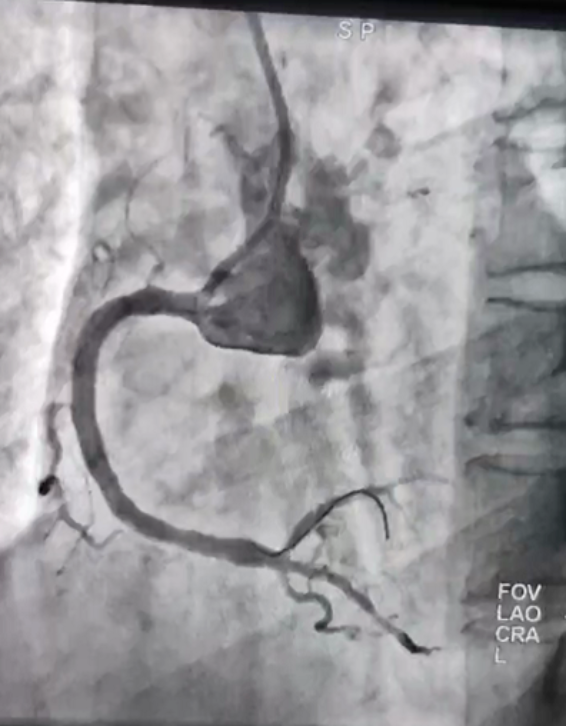

并进行支架植入术,支架植入术属于微创手术,经过精心的手术,支架在心血管内科主任邸爱群的熟练操作下下,顺利进入心血管狭窄位置,医护人员协同努力,成功为张先生的急性下壁心梗进行了血栓抽吸术和支架植入术。

支架后血运通畅